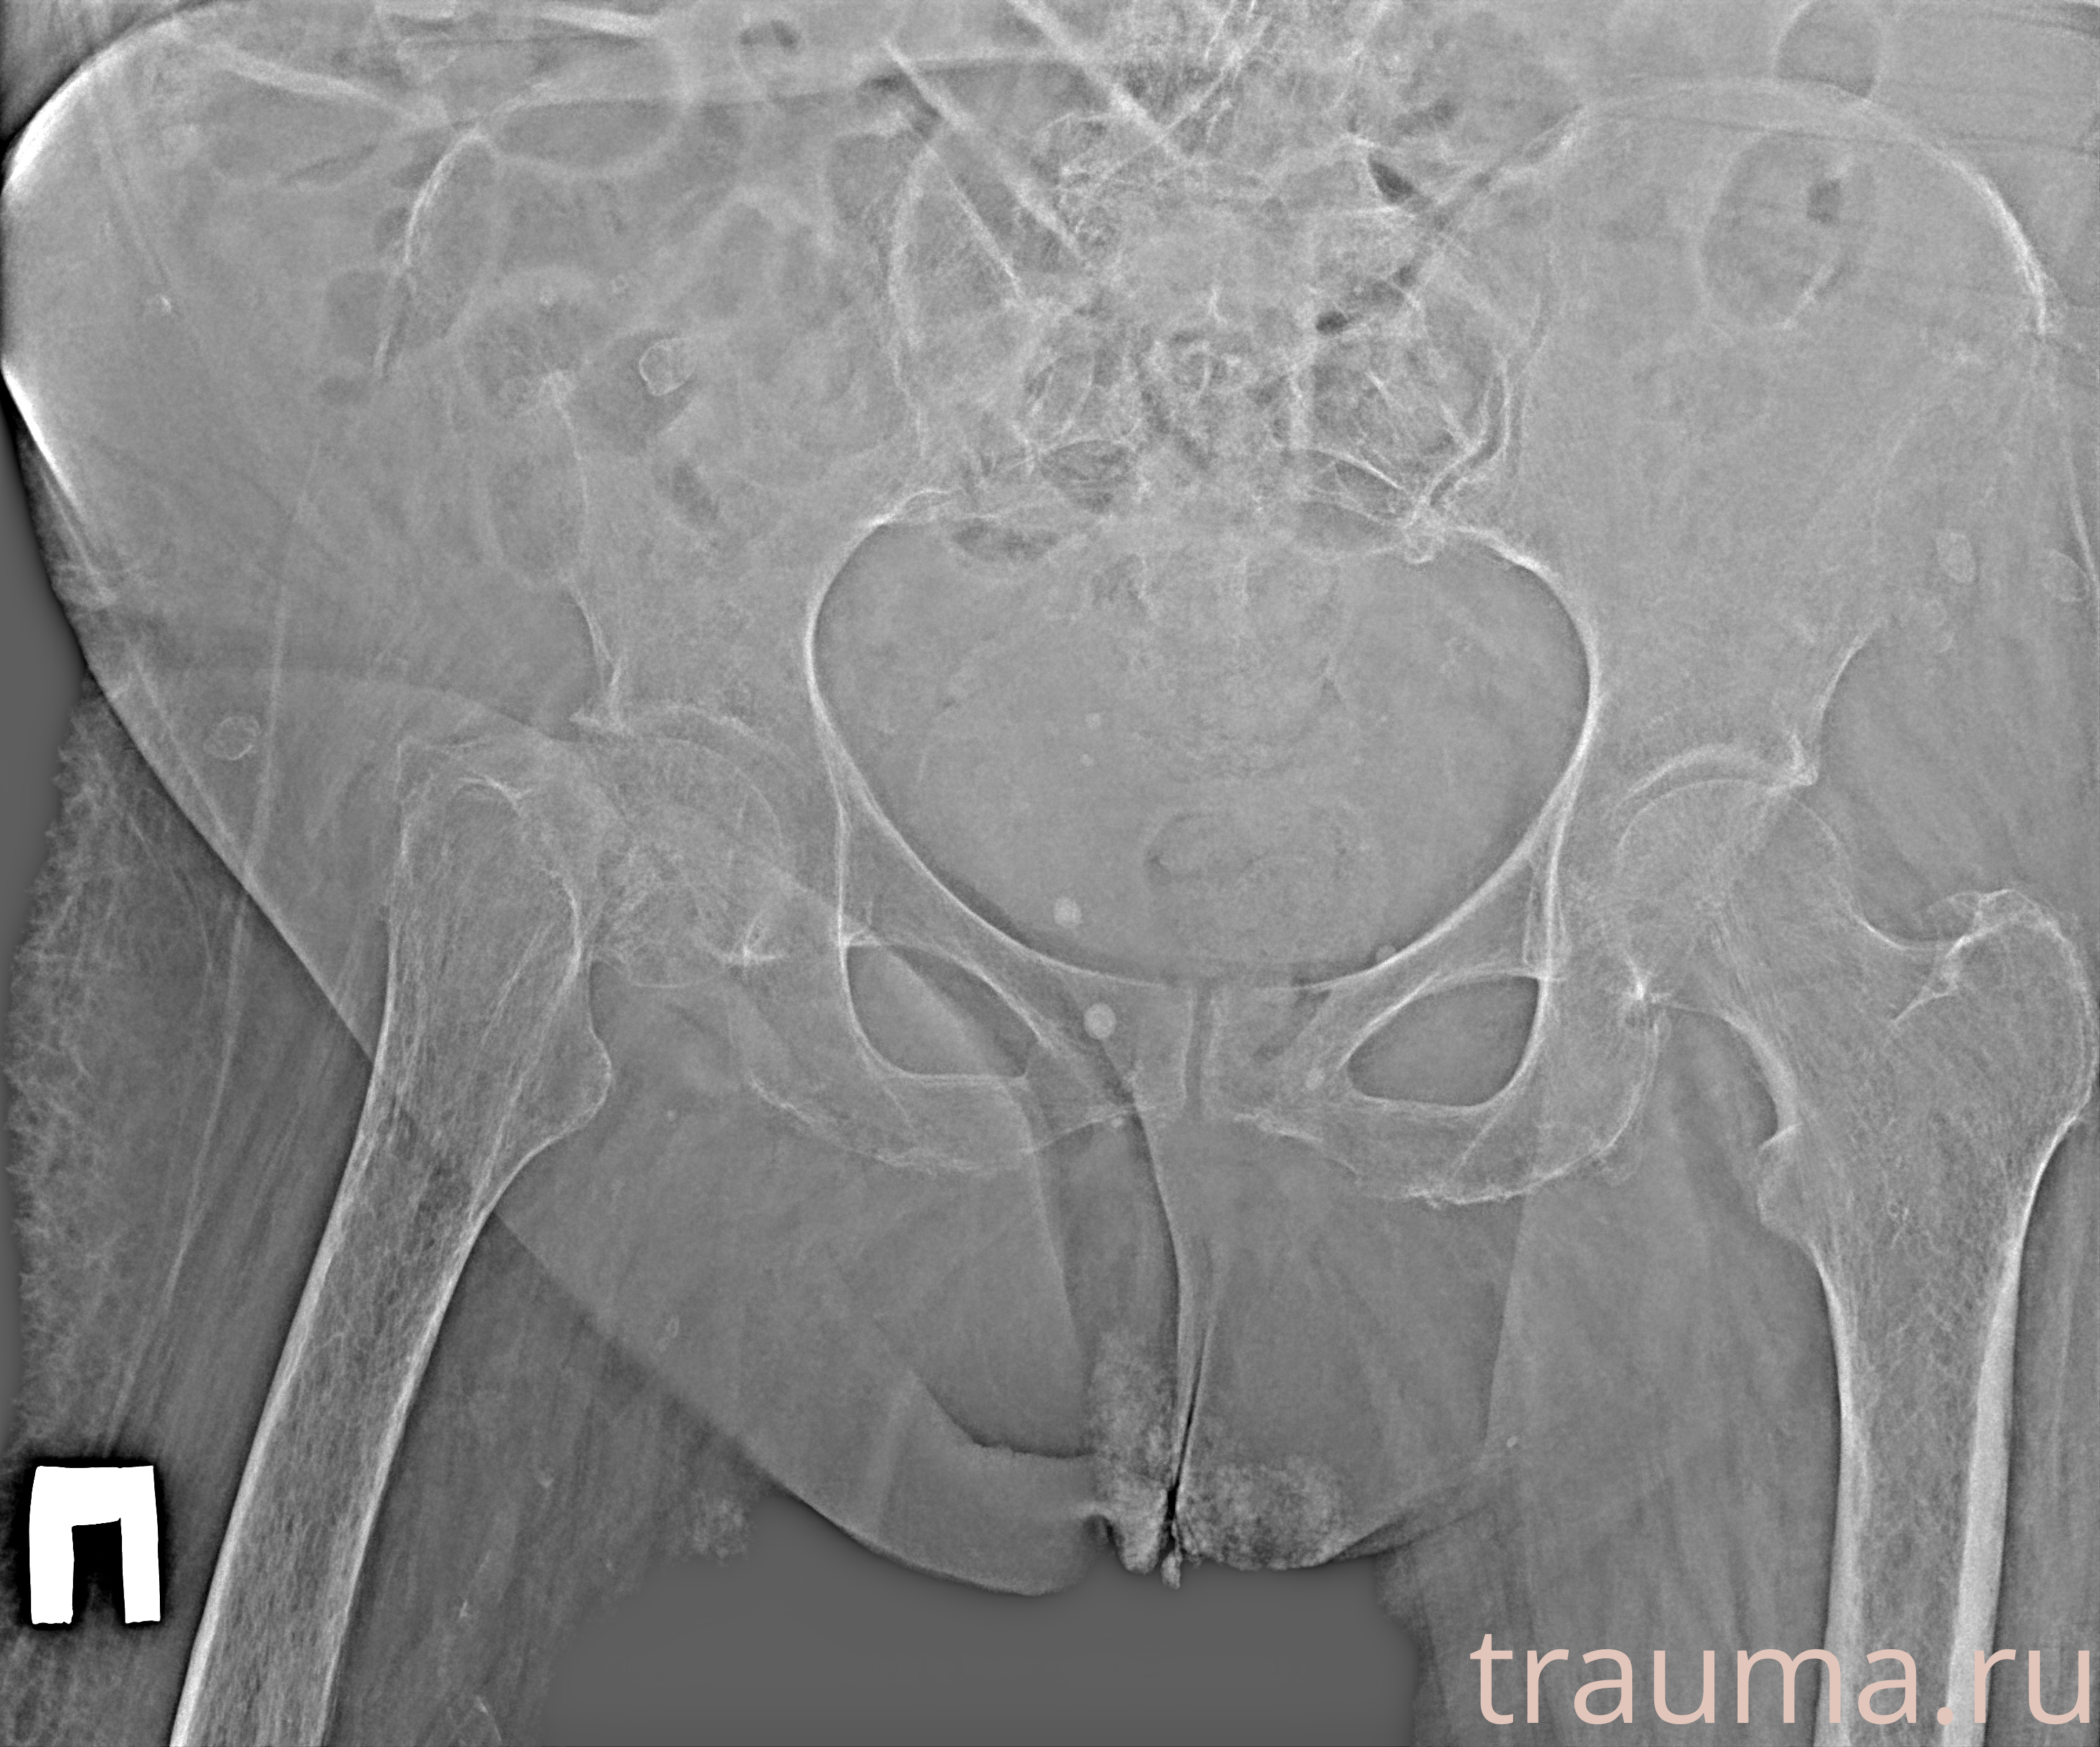

Рентгенограммы

Рентген на дому: по вашему адресу приезжает врач-рентгенолог, травматолог-ортопед с мобильным рентгеновским аппаратом, проводит диагностику травмы или заболевания, делает необходимые рентгенограммы, дает рекомендации по дальнейшему лечению. Получить качественные снимки в домашних условиях возможно благодаря уникальной методике, разработанной МосРентген Центром для института  Склифосовского